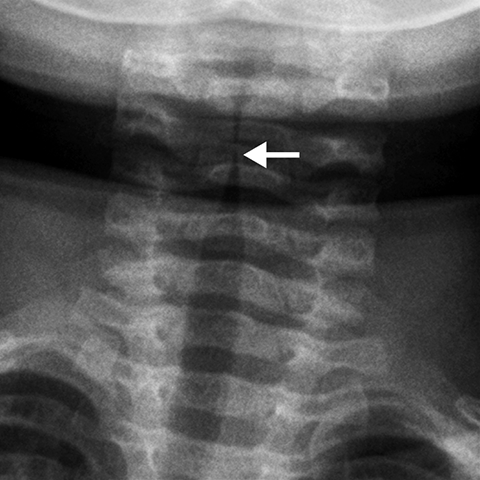

Croup [1 of 2]